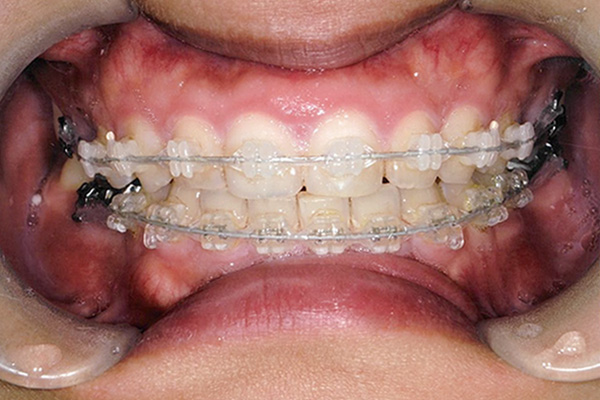

3ヶ月後

10ヶ月後

24ヶ月後

42ヶ月後